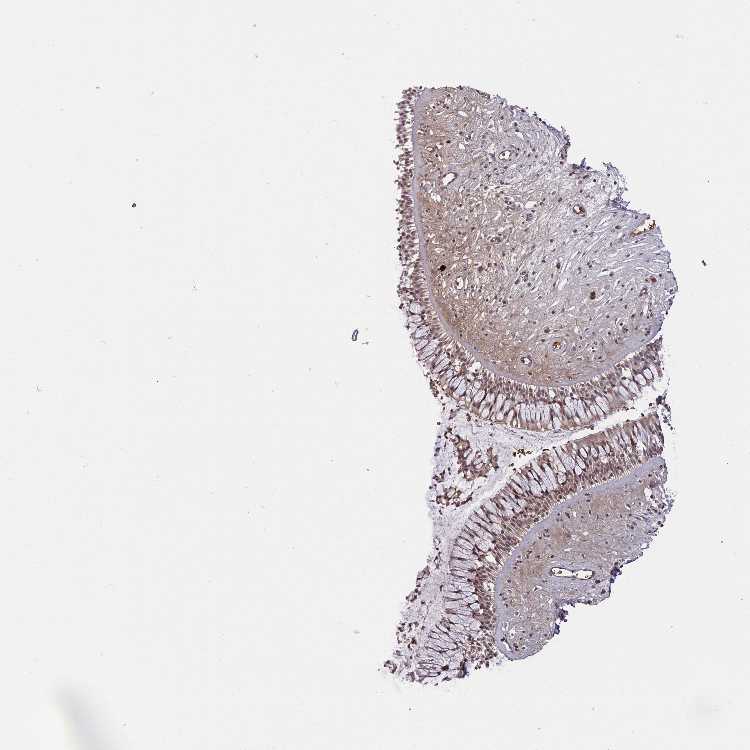

NASOPHARYNX - Antibody stainingi

Antibody staining in the annotated cell types in the current human tissue is reported as not detected, low, medium, or high, based on conventional immunohistochemistry profiling in selected tissues. This score is based on the combination of the staining intensity and fraction of stained cells.

Each image is clickable and will lead to virtual microscopy that enables deeper exploration of all samples and also displays staining intensity scores, fraction scores and subcellular localization as well as patient and tissue information for each sample.

Antibody HPA046833Antibody CAB004545

Respiratory epithelial cells LowNot detected